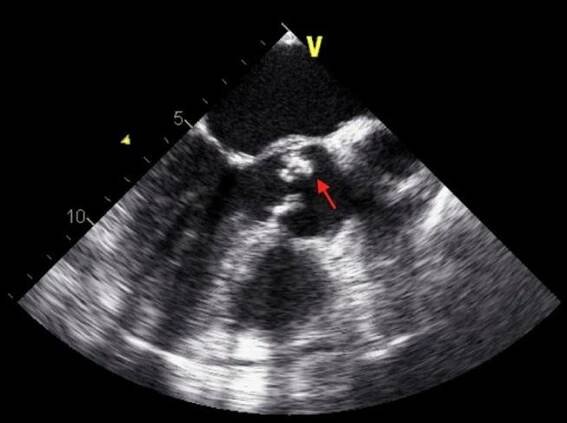

Endokarditida - vegetace na aortální chlopni na TEE

Infekční endokarditida je zánět vnitřního povrchu srdce neboli endokardu, který je způsobený mikroorganismy a postihuje zejména srdeční chlopně.

Infekční endokarditida je infekční zánět srdeční nitroblány. Onemocnění přibývá u jedinců bez srdečního onemocnění a s nezměněnými chlopněmi, obvykle po lékařských nitrožilních výkonech, u narkomanů, a dále u pacientů s umělými chlopněmi.